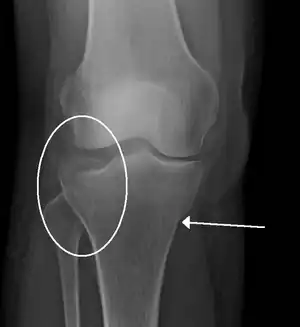

| A severe tibial plateau fracture with an associated fibular head fracture | |

Lipohemarthrosis (presence of fat and blood from bone marrow in the joint space after an intraarticular fracture) seen on X-ray in a person with a subtle tibial plateau fracture

Lipohemarthrosis due to a tibial plateau fracture

A tibial plateau fracture seen on X-ray